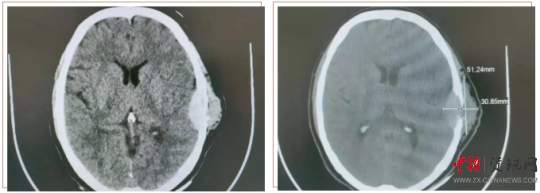

患者王某,女,58歲。半年前,患者用手觸摸頭部左耳上側(cè)時(shí),發(fā)現(xiàn)一個(gè)小腫物,如花生米大小,當(dāng)時(shí)沒太在意,十幾天前發(fā)覺腫物突然增大,由原來的1cm左右增大至5cm左右,且有壓痛感。于是來到上蔡縣人民醫(yī)院就診。神經(jīng)外科副主任楊學(xué)義接診后,安排患者做顱腦CT檢查,結(jié)果顯示:左側(cè)顳部占位侵犯腦膜及顱骨骨板,需要手術(shù)治療。遂收入神經(jīng)外科,經(jīng)過充分的術(shù)前討論,制定周密的手術(shù)方案后,由神經(jīng)外科主任周學(xué)良、副主任楊學(xué)義、主治醫(yī)師商文山、楊慶華歷時(shí)3個(gè)小時(shí),成功將患者左側(cè)顳部5×4cm腫瘤完全切除,同時(shí)行“硬腦膜修補(bǔ)、顱骨修補(bǔ)手術(shù)”,術(shù)中精準(zhǔn)解剖,精細(xì)操作,避免了血管及神經(jīng)等副損傷。術(shù)后顱腦CT掃描顯示:腫瘤完全切除,無腫瘤組織殘留。患者現(xiàn)已痊愈出院,未出現(xiàn)神經(jīng)功能障礙。目前正在隨訪中。

顱腦 CT 掃描顯示(下圖):左側(cè)顳部占位侵犯腦膜及顱骨骨板。